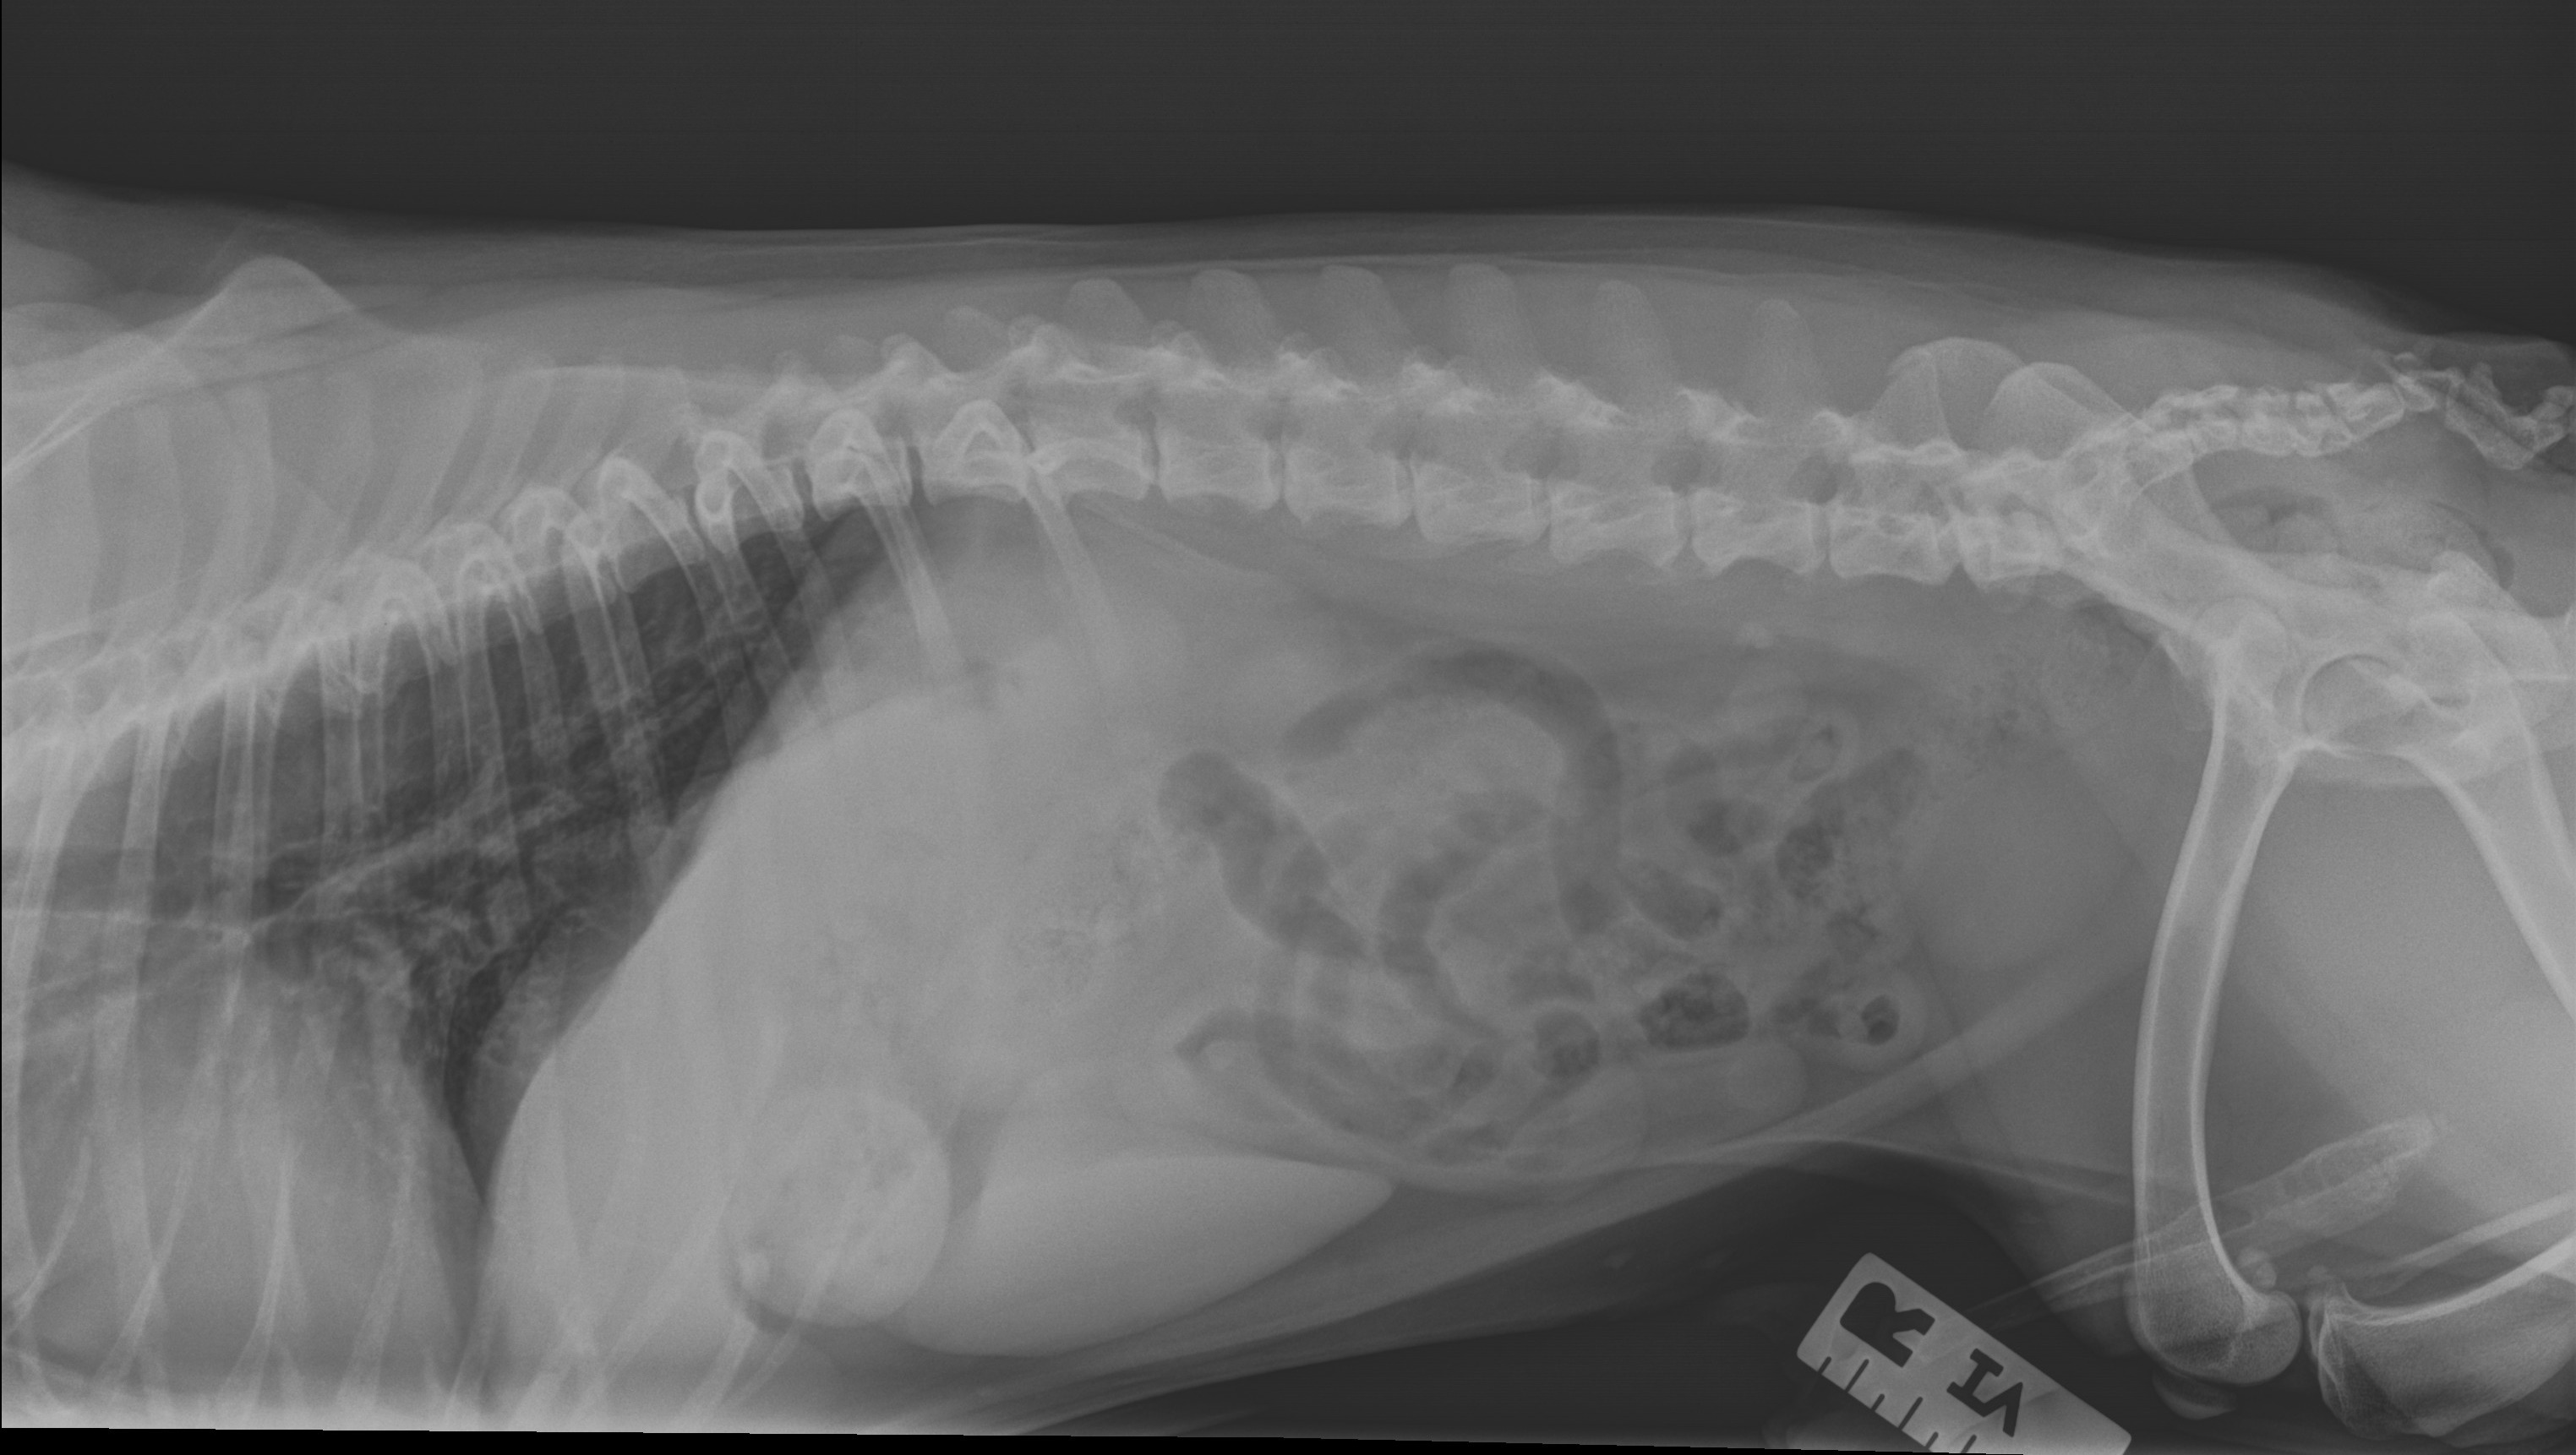

Hello my name is Cooper. I am a 7 year old chocolate Boston Terrier. Up until 2 weeks ago, I was a very energetic loving dog. I loved to play with my two Boston Terrier sisters. My mom went to let us out to potty one morning, I couldn't move off the sofa. My mom put me down on the floor, I just collapsed over. I was shaking and yelping in pain. My mom rushed me to an emergency vet clinic. For them to say everything look fine. Two days later I just got worse. So my mom took me to a different emergency vet hospital. There the vet told my mom I possibly had IVDD. Dr sent me home with a muscle relaxer and pain medication. It has been a week later. I am not getting any better. Dr told my mom that I do have IVDD. There are 5 stages of IVDD. I am near stage 3. The dr gave my mom a diagnosed plan to treat me. It is going to cost anywhere from $4000 to $8000 to get me running and playing again.

Alittle info about IVDD: Intervertebral disc disease in dogs is a medical condition that causes spinal compression and requires immediate attention. Compression of the discs within the spinal vertebrae causes severe spinal and nerve pain, and sometimes even paralysis.

An intervertebral disc is essentially the cushion between each of the bones within a dog’s spinal cord. The spine is made up of individual bones called vertebrae, and in between each vertebrae sits a disc shaped material that has a firm, fibrous covering on the outside with a gelatinous like substance on the inside of the disc. These discs help cushion and protect the bones of the spine. A dog’s spinal cord is comprised of the following bones:

There are two types of IVDD that can occur within dogs. Cooper has type 1.

Type I: This form of IVDD occurs when the intervertebral disc becomes calcified and then suddenly protrudes from within the spine, which causes very painful pressure along the spine and associated nerves. Also known as a herniated disc, often something as simple as a wrong movement can cause the calcified disc to protrude. Additionally, the disc can protrude in different directions, thus causing different types of pain. If the disc protrudes upward, it can cause bruising and compression of the spine. If it protrudes sideways, it will hit the nerves where they exit the spinal column. Either type of protrusion causes sharp pain and a reduction of nerve function.

There 5 stages Cooper is in between 2 and 3.

Stage II: Your dog will have moderate to severe pain within the neck or lower back areas.

Stage III: This stage is when a dog experiences partial paralysis, also known as paresis. This may result in difficulty walking, incoordination, or an inability to stand.